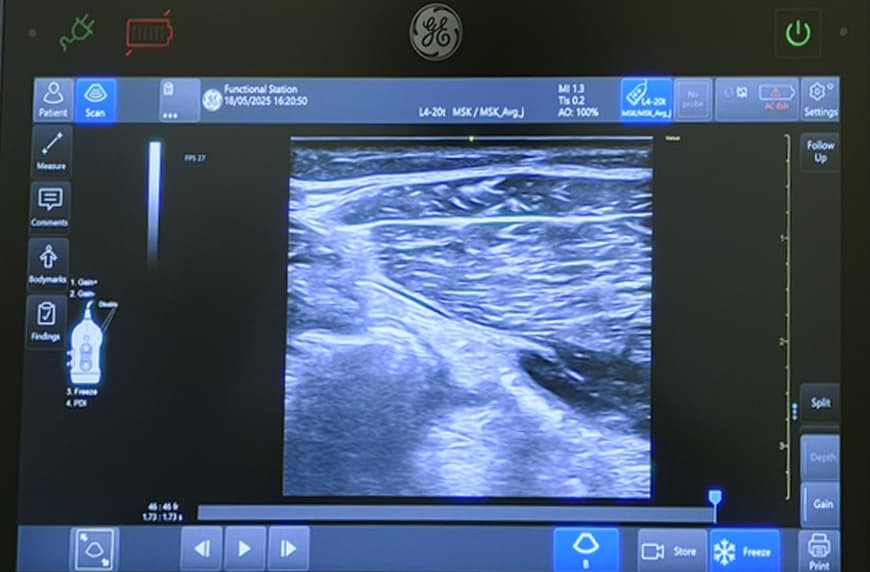

筋肉・腱・関節の状態を痛みなくリアルタイムで可視化し、施術やトレーニングに活かしています。症状が現れる前の「未病」状態も発見できるため、ケガの予防やパフォーマンス向上、リハビリの精度向上に貢献します。